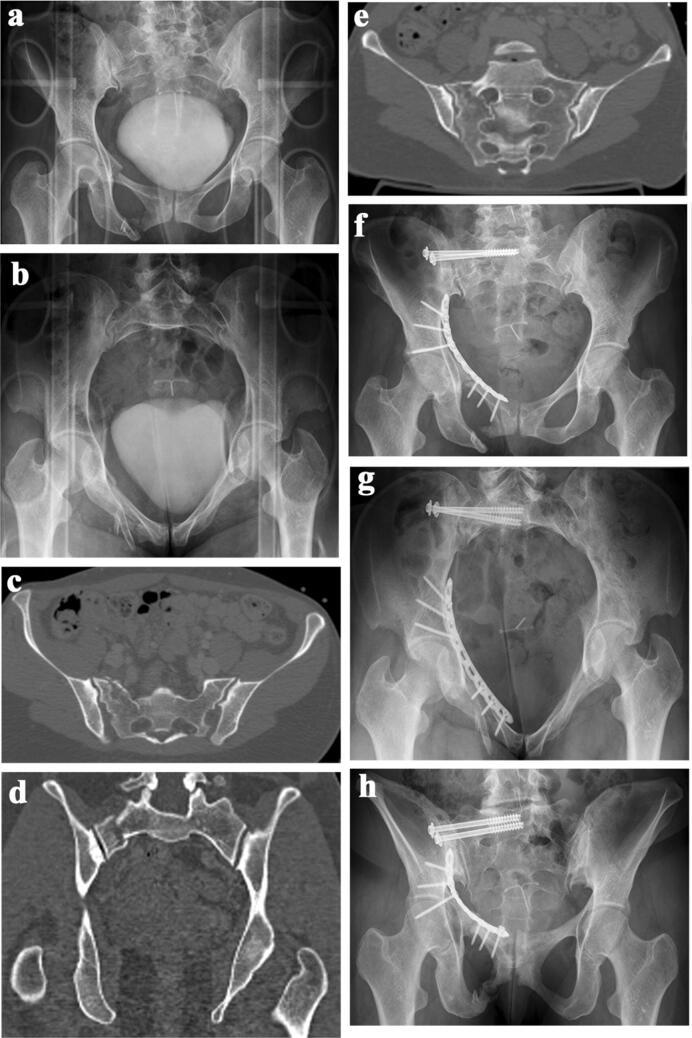

During a 10-year period (2005-2014), 98 patients between the age of 18 and 65 years received 207 iliosacral screws in 101 procedures. Average patient age was 43.2 years. There were 46 Type B and 40 Type C injuries in the AO/OTA classification, nine patients had a fragility fracture of the pelvis. In three patients, primary radiological data were missing. The indication for surgical treatment was a sacral fracture in 97 patients, a pure iliosacral dislocation in 37 patients and a fracture-dislocation in 31 patients. 70 procedures were performed with the patient in supine position, 31 with the patient in prone position. Surgery was done in a minimal-invasive technique in 76 patients, in 22 patients an open reduction was necessary before screw insertion. 81 patients received a unilateral, 17 patients a bilateral screw osteosynthesis. 199 screws were inserted in S1, only eight screws in S2. 65 patients received two screws unilaterally, ten patients two screws bilaterally. There were no vascular or neurologic complications. During in-hospital stay, there were seven complications, which needed 12 operative revisions: three wound infections, two hematomas, one screw malalignment and one early screw loosening. In 28 patients with 56 iliosacral screws, a pelvic CT-scan was performed during follow-up. A penetration of a cortical layer was diagnosed in 20 of these screws. All penetrations were seen in double screw osteosynthesis of S1. In none of the patients, complaints could be explained by the malalignment of these screws. Five operative revisions were performed during follow-up: two for screw loosening, two for fracture healing problems and one for screw malalignment. Metal removal was performed in 39 patients with 75 screws. 2D-fluoroscopic-guided iliosacral screw osteosynthesis is a safe and efficient procedure in clinical practice.

A thorough preoperative evaluation of the morphology of the upper sacrum and careful operative procedure are indispensable. Fluoroscopic views in AP, lateral, inlet and outlet must allow recognition of all anatomical landmarks. The indication for double screw osteosynthesis in S1 should be taken with caution. Screw malalignments do not inevitably correlate with complaints.